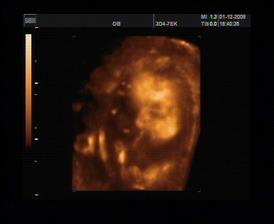

8.10.2008 ultrazvuk ve 20tt. Všechno probíhá normálně, prcek roste tak jak by měl. Měříme cca 20cm, váha 450 g. Hlavička odpovídá na 19+4, takže datum porodu nám potvrdili na 28. února. Chtěli jsme vědět pohlaví, ale bobek na nás vystrčil prdýlku a máme si prý trhnout ☹